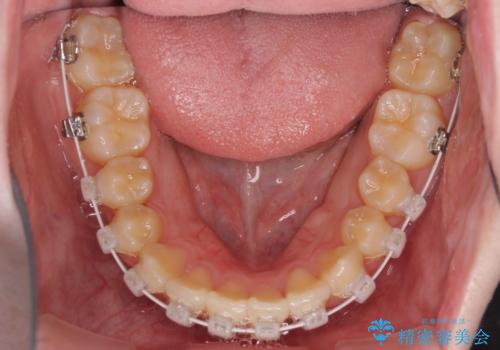

治療途中で大学受験があり、来院できない時期がありましたが、2年以内で満足のいく歯並びを達成することができました。